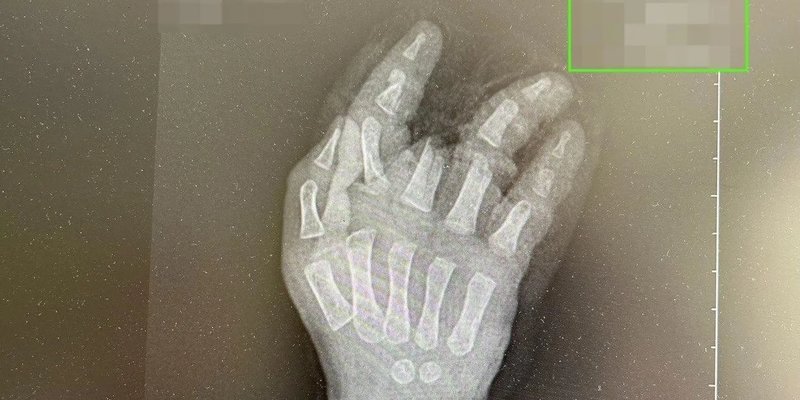

В Башкирии годовалый малыш засунул руку в работающую мясорубку, пока мама отвлеклась на несколько минут.

У него травмированы пальцы, медики под наркозом извлекли руку мальчика из мясорубки. Первую помощь оказали ребенку в районной больнице, после чего его госпитализировали в Уфу.

Медики провели ревизию раны, наложили гипс. Мальчику предстоит реконструктивная пластика кисти.